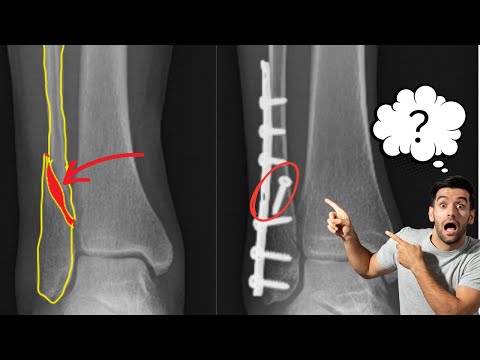

Ankle Fractures, Surgical Treatment ,tactics - Everything You Need To Know - Dr. Nabil Ebraheim

How Surgeons Fix This Ankle Fracture!

Operative treatment of ankle fractures

Bimalleolar/Ankle Fractures: Some Tips to Avoid Malalignment

Ankle Fracture Surgical Stabilization Using the FibuLock® Nail